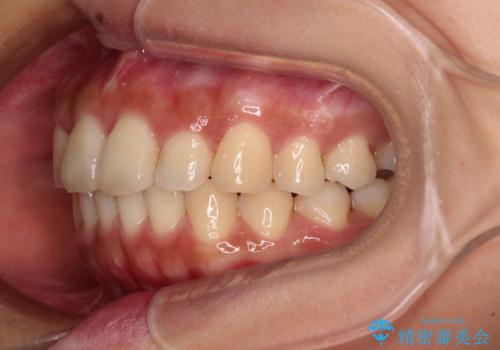

【モニター】歯列が狭くデコボコが気になる 急速拡大装置を用いたインビザライン矯正

- 奥歯の咬み合わせと治療を放置したまま奥歯を気にして来院された患者様です。

上顎骨の幅が下顎骨よりも小さいので、拡大装置により骨幅を広げて上下関係を改善し、その後インビザラインにて歯並びを整えることとしました。

矯正治療後には土台のままとなっている歯をセラミッククラウンにて補綴治療を行うこととしました。

上下の骨幅を改善したことで、スムーズに歯列矯正を行うことができました。

土台のまま放置されていた歯は土台の状態で咬み合っていましたが、急速拡大を行った際に咬み合わせが著しく挙上されたため、その際に土台を大きくすることで咬み合う歯との距離を確保しました。